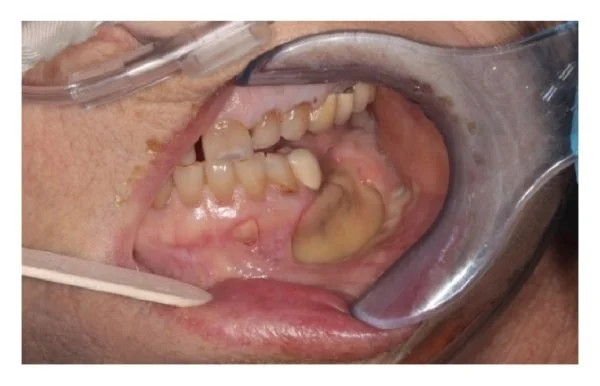

Ide o stav, pri ktorom sa kosť v oblasti čeľuste nedokáže správne hojiť a postupne odumiera. Môže sa prejaviť:

- bolesťou

- opuchom

- nehojacou sa ranou

- obnaženou kosťou v ústach